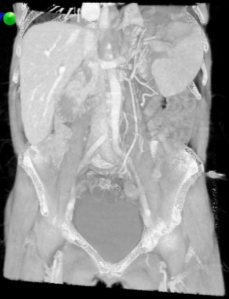

Figure 2: Three-dimensional image reconstruction of splenic torsion from CT data set.

Virtual Reality (VR) image depiction using Perspectus software, demonstrating the 360-degree rotation of the splenic artery and vein.